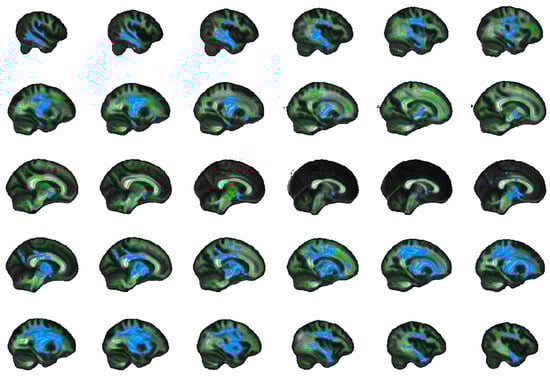

2.5. Exploratory Whole Brain Results

4.8. Exploratory Whole Brain Analysis

| Tracts | Side | Peak Voxel (MNI) | F-Statistic (TFCE) | Cluster Size > 100 (Voxels) | Cluster p-Value | ||

|---|---|---|---|---|---|---|---|

| x | y | z | |||||

| FA | |||||||

| SFOF | Left | −22 | −2 | 19 | 19.5 | 10,610 | 0.001 |

| ILF | Right | 45 | −11 | −27 | 14.2 | 6452 | 0.003 |

| UNC, IFOF | Right | 18 | 24 | −12 | 13.8 | 669 | 0.015 |

| AD | |||||||

| Unclassified | Left | −10 | −1 | −14 | 17.3 | 12,958 | 0.001 |

| ILF | Right | 40 | −22 | −21 | 11.5 | 1739 | 0.014 |

| Forceps minor | Right | 12 | 31 | 8 | 10 | 1522 | 0.028 |

| UNC, IFOF | Right | 28 | 14 | −10 | 9.84 | 786 | 0.03 |

| Unclassified | Right | 1 | 10 | 14 | 7.64 | 188 | 0.047 |

| Forceps minor | Left | −12 | 29 | −12 | 9.1 | 157 | 0.042 |

| SLF | Left | −34 | −37 | 21 | 10.3 | 141 | 0.038 |

| ATR, IFOF | Right | 23 | 26 | 23 | 5.94 | 141 | 0.047 |

| MD | |||||||

| ATR | Left | −11 | −17 | −2 | 18.1 | 31,113 | 0.001 |

| RD | |||||||

| ATR | Left | −23 | −2 | 17 | 18.8 | 14,709 | 0.001 |

| ILF | Right | 45 | −10 | −28 | 15.3 | 6641 | 0.004 |

| UNC, IFOF | Right | 18 | 24 | −12 | 13.4 | 209 | 0.039 |